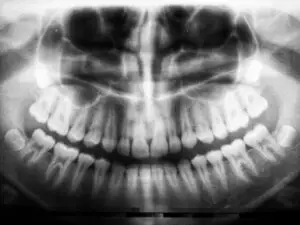

A panorex is a very impressive piece of imaging machinery in that it is capable of identifying many issues and structures that a normal x-ray is not. Initially you will sit in a chair with your chin on a small ledge. Once positioned in the machine, it will rotate around your entire head taking a full 360 degree view of the teeth, head, sinuses and bones.

The ability to view the full structure of your head as a whole is very informative to the dentist. It will allow us to see any potential problems and make sure that everything is functioning as it should be. The panorex is capable of viewing specific types of structural problems, infections or asymmetry among many others.